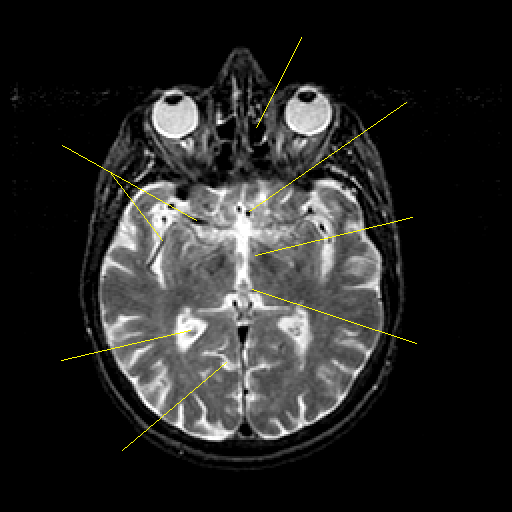

T2-weighted structural MR: Slice 25

Slice 25

Pointers

Labeled